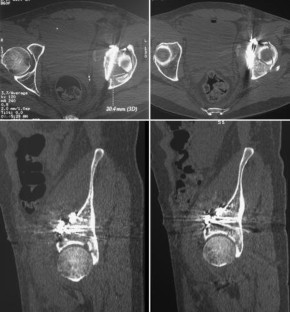

Vordere Pfeilerfraktur des Acetabulums mit dorsaler Impression

Anterior column fracture of the acetabulum with dorsal impression

Es wird ein ungewöhnlicher Fall einer vorderen Pfeilerfraktur des Acetabulums mit ausgedehnter Impression im Bereich des hinteren Pfeilers beschrieben. Nach primärer Osteosynthese über einen ilioinguinalen Zugang erfolgt die Reposition der dorsalen Impressionen über einen hinteren Zugang mit Repositionskontrolle mittels chirurgischer Hütluxation.

An unusual case of an anterior column fracture of the acetabulum with extended marginal impaction at the posterior column is presented. Fracture fixation was primarily performed by an ilioinguinal approach followed by a posterior approach with surgical dislocation of the hip to reduce the impacted fragments.